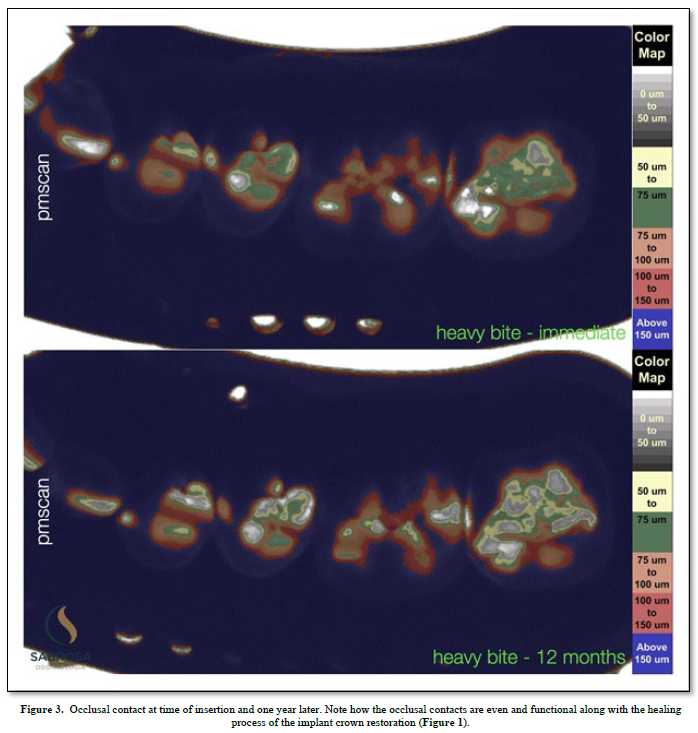

Proprioception is used to navigate space in order for a subject to find a place to make physical contact. (1) An implant with no periodontal housing exhibits little or no proprioception. It has no periodontal housing and no touch or pressure sensors. An opposing functioning tooth with periodontal support is proprioceptive. It is touch sensitive (2). The pressure sensors detect motion and help to reposition and maintain the tooth in a functioning occlusal position. There is little or no information concerning implant proprioception. In a functioning dentition teeth find their position by adjusting to the existing teeth in occlusion. An under occluded implant crown cannot adapt to an existing occlusion without planned occlusal contact guidance. Positional direction and intensity of contact are left to chance. We, as humans, have five senses one of which is touch. Sharks have six senses one of which is touch from a distance (3). Weak electrical signals are used to make contact from afar. Humans can not touch without making physical contact. An implant crown that is under articulated cannot fit into an opposing dentition without making occlusal contact. Total implant placement procedures and restorative healing results are shown (Figure 1). Without implant restorative occlusal contact adjacent teeth and the surrounding dentition adapt to an altered occlusion. Stress distribution is uneven because fewer teeth maintain the occlusal load. Missing limb syndrome where the patient assumes limb retention upon fitting a prosthetic device may be applied to replacing missing teeth where the patient upon tooth replacement immediately assumes past functioning habits. In this case, as shown, tooth and jaw movements related to an altered occlusion are slight but tooth movements are discernible. The occlusal patterns have shifted. There is an uneven amount of occlusal contact upon the second molar (Figure 2). One year later the occlusal contact areas are more evenly distributed. The implant restoration is in functional occlusion. The second molar now fits into the occlusal scheme as does the first molar implant restoration. The teeth have been realigned (Figure 3). In order to plan the occlusion of this implant the clinician (CES) adjusted the surface of the milled zirconia crown (Cerec) prior to completion so that it would just make occlusal contacts upon hard closure (Figure 2). Clinical acumen dictates how much occlusal clearance is required. It is estimated that teeth intrude up to 100 microns upon occlusal loading (3). We assume that when the tooth is fully loaded it will make occlusal contact with its antagonist but when not loaded it will not make contact (4) (Figure 2). To verify contact and non-contact we make a silicone inter occlusal record at the time of insertion (5). The impression is removed and immediately processed using a specially made occlusal scan which includes a direct current light box positioned six inches from an enclosed overhead camera which is connected to an image producing means for recording and interpreting various thicknesses of impression material. The results using image analysis (Image J) can be assessed numerically or viewed using assigned colors that relate to the numbers (6). Two hundred fifty-six pixels is the baseline and the color is white (contact).